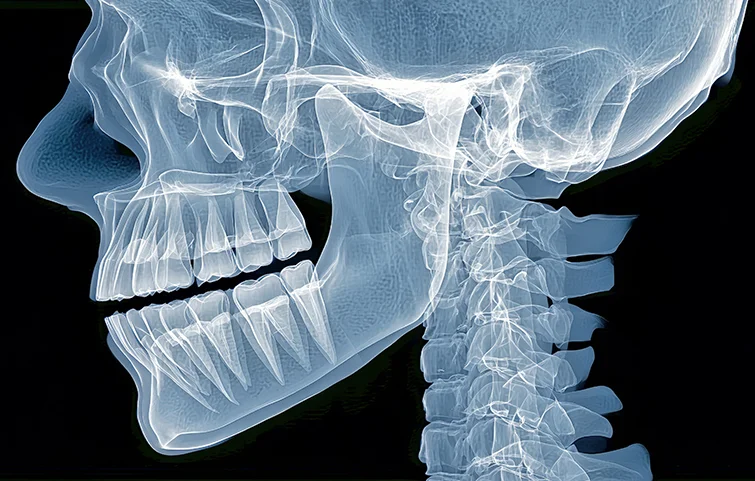

Jaw fractures, particularly of the mandible or maxilla, are commonly caused by trauma from accidents, sports injuries, or violence. Diagnosis begins with a thorough clinical evaluation. The patient may present with facial swelling, bruising, pain, difficulty in opening or closing the mouth, malocclusion (improper bite), and numbness due to nerve involvement.

Physical examination includes assessing jaw alignment, mobility, and palpation for stepoffs or crepitus. Intraoral examination checks for bleeding, lacerations, or tooth mobility. Imaging is crucial for confirmation. A panoramic X-ray (orthopantomogram) is a common initial tool to visualize the mandible. However, computed tomography (CT) scans are the gold standard for complex fractures or midface injuries, providing detailed 3D visualization of bone involvement.

In some cases, cone-beam CT (CBCT) may be used, especially in dental settings, to assess smaller or localized fractures. If the fracture involves the condyle or temporomandibular joint, additional TMJ-specific views may be needed. Associated injuries such as dental fractures or airway compromise should also be evaluated.

Treatment decisions are guided by imaging findings, location of the fracture (e.g., angle, symphysis, condyle), displacement, and patient symptoms. The goal of diagnosis is not only to confirm the fracture but also to assess complications, such as infection, nerve damage, or airway obstruction, ensuring timely and appropriate surgical or non-surgical intervention.